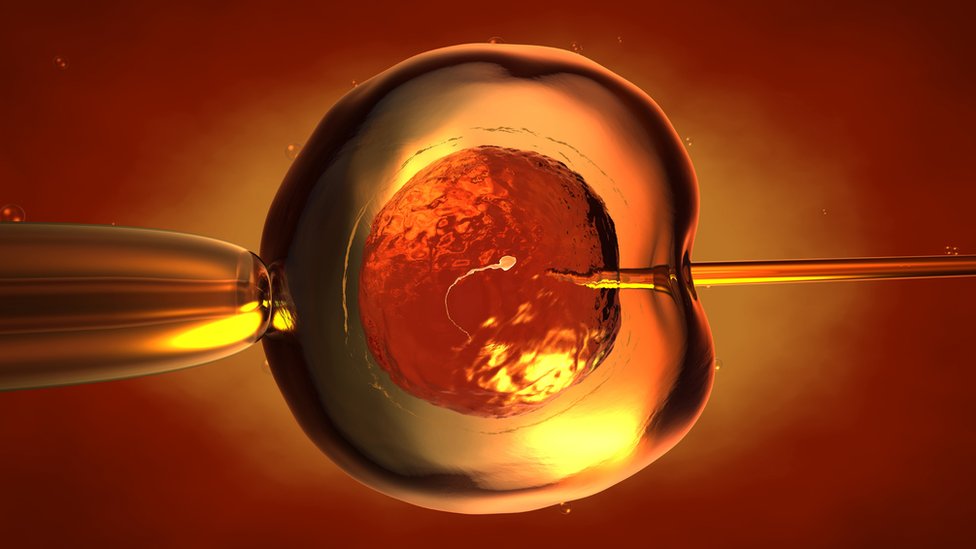

Istraživanje vodi Hiromicu Nakauči sa Univerziteta u Tokiju i Stenforda. Tokom postupka, naučnici će ubrizgavati ljudske matične ćelije u modifikovane embrione pacova i miševa kako bi stvorili pankreas.

Tehnika podrazumeva genetsko modifikovanje životinjskih embriona tako da se odstrane geni povezani sa proizvodnjom određenog organa – u ovom slučaju, pankreasa, ali u budućnosti možda čak i jetre i bubrega.

Naučnici potom ubrizgaju u životinjski embrion ljudske matične ćelije. A odsada će im biti dopušteno da puste da se embrioni razviju do kraja.